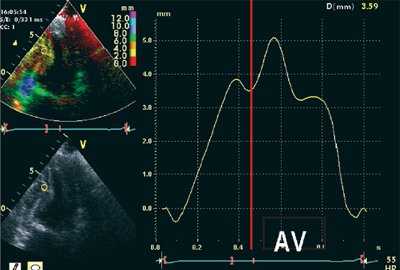

ЭхоКГ (стандартная и в режиме тканевой допплерографии) проводилась на ультразвуковой диагностической системе Vivid Five фирмы General Electric (США) секторным датчиком c частотой 3,75 МГц. Исследовалось движение продольных волокон миокарда в проекциях по длинной оси левого желудочка из верхушечного доступа. Тканевая допплерография проводилась в 4-, 3- и 2-камерной проекциях в каждом из 16 сегментов левого желудочка и в 4 точках митрального кольца: у основания заднеперегородочной, боковой, нижней и передней стенок левого желудочка. Оценивались следующие параметры.

![Тканевая допплерография в норме. У больного с постинфарктным кардиосклерозом регистрируется высокоамплитудный пик постсистолической скорости (Sps)]()

Вертикальная линия (AV) на рис. 3-5 соответствует времени закрытия аортального клапана. На представленных графиках также отмечается наличие базально-верхушечного градиента (снижение пиковых миокардиальных скоростей, продольного систолического смещения и деформации от основания к верхушке левого желудочка).